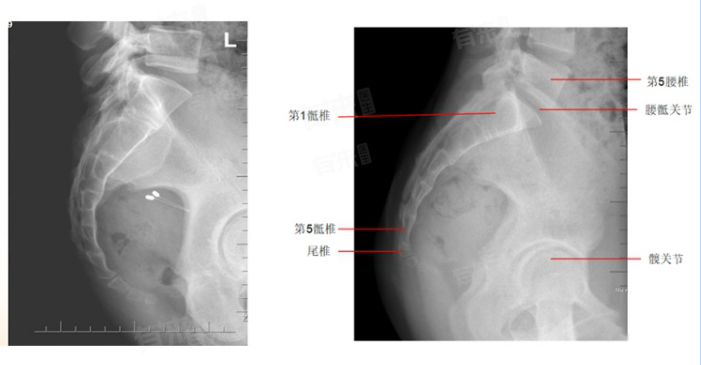

- 骶骨位于腰椎的下方,骨盆的后方,是构成骨盆后壁的重要骨骼之一。骶骨由五块骶椎融合而成,形态呈三角形,具有底部、侧部、尖部、骨盆面及背侧面等多个解剖结构。

- 尾骨位于骶骨的下方,由三到五块退化的尾椎融合而成,形状类似锥形。尾骨虽然在人体中相对短小,但同样具有支撑和稳定的作用。